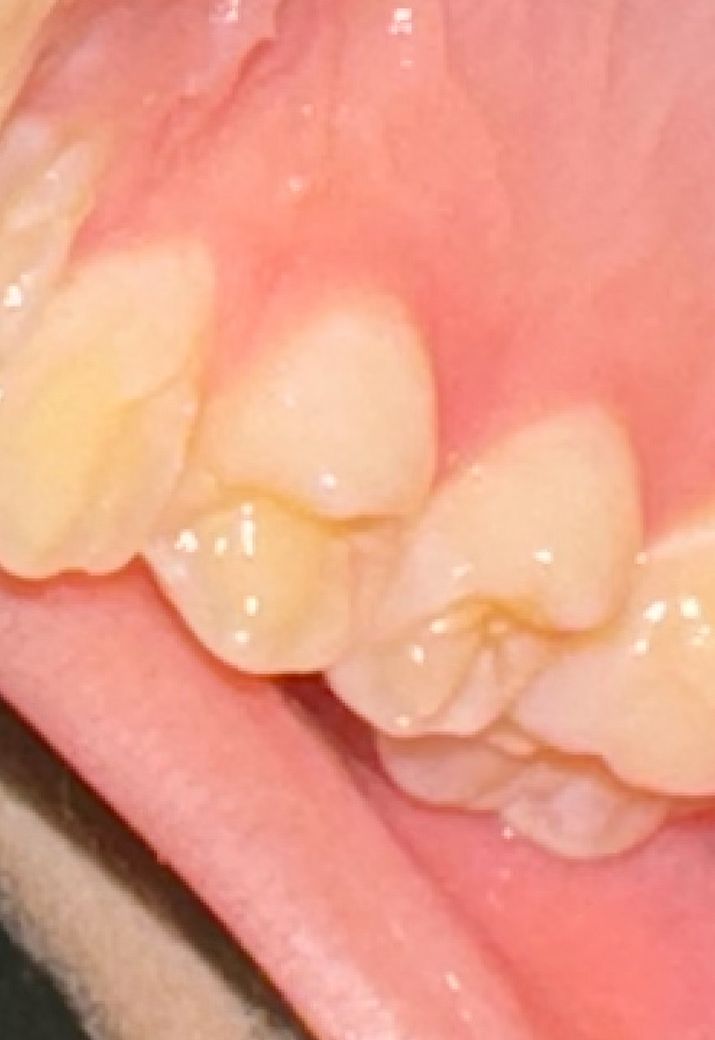

일주일 전부터 씹을때 약간의 통증? 불편감이 있었어요

그냥 약간 거슬리는 정도지 별로 심하지도 않아서 양치만 평소보다 꼼꼼히 하고있는데 병원을 가야 할 수준의 치은염일까요?

사진상으로는 별다른 문제는 보이지 않습니다.

치은염이면 붓거나 피가 나는 증상이 나타나는것이 보통이며 곧 괜찮아질것 같습니다

해당 부위의 잇몸에 약간의 발적이 보이기는 하나 치은염에 대한 정확한 진단을 위해서는 치과 방문 후 정확한 진단을 해야 합니다. 단순히 사진만으로는 판단이 어려우며 임상 검사 등을 통해서 해당 부위를 점검해야 합니다.

사진상으로 크게 문제가 있어 보이지는 않으나, 잇몸에 통증 및 출혈 붓기가 있는 경우에는 치과에 방문하여 상태를 확인하고, 스케일링 및 적절한 치료를 받길 권합니다.

사진으로 봤을 경우에는 크게 문제가 있어 보이진 않습니다. 해당부에서 출혈이 되거나 하면 잇몸에 염증을 유발하는 물질이 있는 것이니 양치질을 꼼꼼히 하시고 치실을 사용해 주세요.

사진상 보기에 잇몸문제는 심각해 보이진 않습니다 씹을때 통증이 있다면 치아 크랙, 충치 등을 의심해볼 수 있을 것 같습니다 치과에서 검진을 해보시기 바랍니다